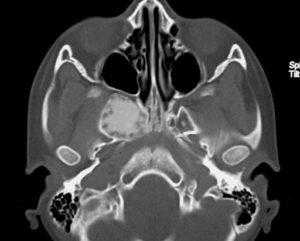

(Слева) При аксиальной «костной» КТ определяются классические признаки фиброзной дисплазии: выраженное вздутие левой верхнечелюстной пазухи с асимметричным выбуханием левой щеки, типичный вид «матового стекла». Обратите внимание на значительное уменьшение объема воздушной полости.

(Справа) При корональной костной КТ определяется фиброзная дисплазия с поражением правой нижней носовой раковины и латеральной стенки носа. Определяется выраженная экспансия раковины с изменениями в виде «матового стекла».